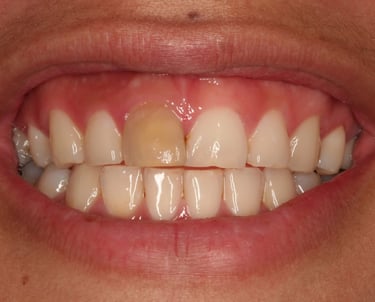

Se realiza cuando un diente se ha oscurecido debido a la muerte de la pulpa. Consiste en colocar un agente blanqueador dentro del diente para devolverle su color natural.

Blanqueamiento interno de dientes